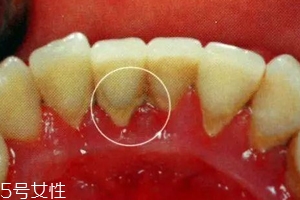

牙結(jié)石是不會(huì)自動(dòng)脫落的,因?yàn)樗卫蔚母街谘例X表面,當(dāng)然有時(shí)候會(huì)有極少數(shù)的牙結(jié)石會(huì)因?yàn)槟闼⒀阑蛘哂醚篮瀯兟?,只是極少數(shù)現(xiàn)象。所以有了牙結(jié)石千萬不能忽視,它不會(huì)像感冒一樣會(huì)自行康復(fù)的,它們只會(huì)在你的牙齒表面沉積下來,日積月累,使你的口腔患上炎癥,這樣只會(huì)導(dǎo)致牙齦炎癥逐漸加重,并發(fā)展為牙周炎,最終導(dǎo)致牙齒松動(dòng)脫落。不要奢求牙結(jié)石會(huì)自動(dòng)脫落了,請(qǐng)重視起來,為了你有一口健康的好牙!

牙結(jié)石第一階段:我們口腔并不是無菌的狀態(tài),口腔內(nèi)有無數(shù)個(gè)細(xì)菌,每當(dāng)我們吃飯食物,食物殘?jiān)诳谇豢p隙超過5分鐘之后就會(huì)形成牙菌斑(牙菌斑就是牙結(jié)石的幼年體)。而且,牙菌斑是粘附在牙齒表面的不易被沖走,這就給更多的細(xì)菌提供肥沃的土壤,一般來說,牙菌斑會(huì)在1-2h迅速增厚,10天之內(nèi)發(fā)展成熟達(dá)到高峰,所以我們應(yīng)當(dāng)在12h左右清除牙菌斑(牙刷,牙線)。

牙結(jié)石第二階段:細(xì)菌有了肥沃的土壤,便會(huì)呼朋喚友前來定居,這時(shí)候,如果你還不注意口腔衛(wèi)生,不及時(shí)清除食物殘?jiān)?,那么,牙菌斑和食物殘?jiān)鼤?huì)在「唾液」的侵泡下經(jīng)過24小時(shí)會(huì)被唾液中的成分「鈣化」,變成「初始」的牙結(jié)石啦。

牙結(jié)石第三階段:然而,牙結(jié)石并不是一成不變的,這種初始的牙結(jié)石會(huì)繼續(xù)沉積、礦化,越積越后,越積越硬,最后牙刷都拿它沒辦法,只能通過醫(yī)用器械將其清除。